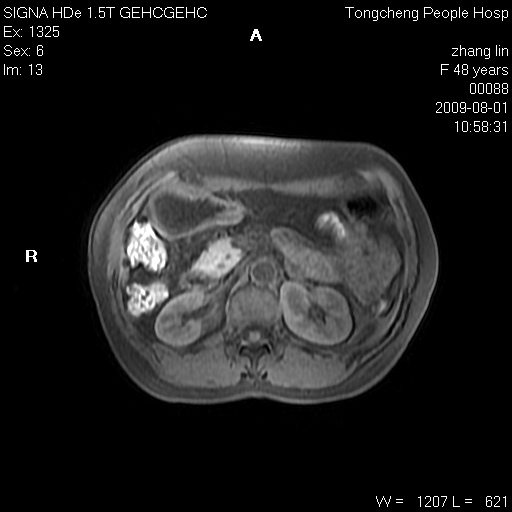

女,48岁。健康体检,彩超发现右肾占位性病变。平素健康。

临床诊断:右肾占位性病变,性质待定(囊肿?肿瘤?)。

上中腹部mr平扫+增强扫描,图像如下:

右肾上极见一类圆形病灶,t1wi呈等信号t2wi呈等高混杂信号,三期增强无强化,边界清---考虑囊肿出血。

同反相位均表现为等信号,病变无强化,考虑含蛋白的囊肿可能,弥散加权相或许有些帮助,

肝囊肿

慢性胆囊炎